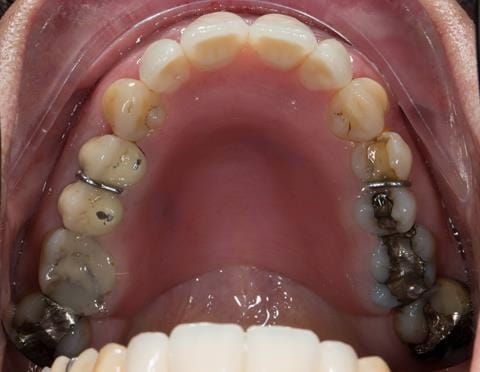

- Extract the upper 2-2 teeth and replace with an interim acrylic based partial denture. Reline the interim denture over 9 - 12 months, replacing with a definitive cobalt chromium based partial denture. The definitive denture would ideally be designed as an occlusal protective splint to reduce the the potential for mechanical wear and breakages of the moderately/heavily restored maxillary dentition. In addition, should further upper teeth require extraction they could be added on to the denture cobalt chromium framework - therefore a new prosthesis would not be required as future teeth are lost. This option would produce an excellent aesthetic outcome. This is the option the patient chose to have.

Following consultation and second discussion appointment the patient chose to have option 3 namely, a maxillary cobalt chromium based partial denture/protective occlusal splint. The clinical situation and treatment process is shown in detail below with photographs. The patient was successfully rehabilitated with this and her quality of life considerably improved. The clinical work was provided by Finlay and the technical work by Rowan.